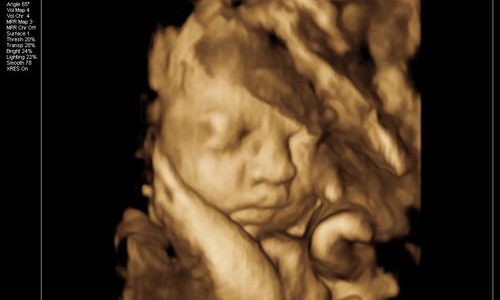

朋友28周的时候叫我陪着去体检,给宝宝照下四维彩照,看看胎儿生长发育过程中有没有变畸形。

因为宝宝在子宫内发育的非常好,活蹦乱跳的。半个小时,朋友拿着四维彩照的照片一言难尽。

这也太丑了吧!朋友说自己和老公的长相都不差,为什么生育的孩子确实塌鼻梁、大鼻孔、厚嘴唇呢?

那山根宽的像座独木桥,整个一阿凡达!欲哭无泪的朋友觉得打击太大,连着好几天都沉浸在悲伤中不能自拔。

真的是这样吗?专家解答说,其实四维彩照出来的成像与宝宝出生后的模样会有一定出入,以下三张图片告诉你。

胎儿的面部脂肪还没有完全堆积,因此从四维看到的脸蛋来说是比较丑的,类似于外星人。头部和身体的占比例大概是2:1,以成年人的视觉来看可不是怪异么。

再者,孕妇拍摄四维的目的,便是排除胎儿面部是否畸形。所以会根据声波成像技术来填充图像,再将口、鼻、眼等细节放大。

但是小宝宝的口耳鼻实在太细节,声波反弹较弱,因此连接到电脑上后会另外填充成像。毕竟四维彩照和我们平时拍照的像素不一样,它是由彩超探头采集到的数据以此合成一个大致的影像。

那么打印出来后自然模糊,边缘不清晰,导致小宝宝的五官和肢体看起来扭曲变形。一定程度上*化丑**了宝宝,让新手爸妈们怀疑人生。

所以,在探头勘测超声波影像时,胎儿在动。加上胎儿整个是泡在羊水里面,左动一下,右动一下,拍摄出来的成像难免会失真。

综上所述,四维彩照出来的胎儿成像,并不会是宝宝实际出生的样子。就和我们去一个餐厅吃饭一样,实物与图片不符。